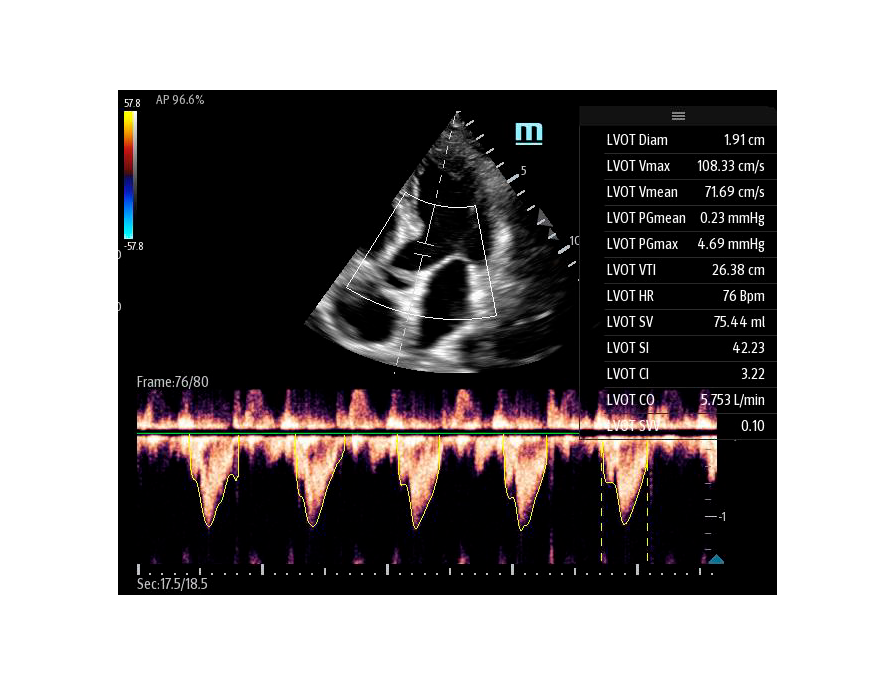

Чтобы использовать уравнение, нужно получить поток выносящего тракта левого желудочка в PW допплере — это достаточно кропотливая работа. В ультразвуковых системах Mindray Resona i9 эта задача решается автоматической оценкой потока выносящего тракта – Smart VTI.

Доктору остается получить 5-ти камерное сечение сердца и нажать одну кнопку на сенсорном экране. Прибор сам выберет расположение контрольного объема, получит спектрограмму и обведет спектр с расчётом всех показателей. Быстро и эффективно.